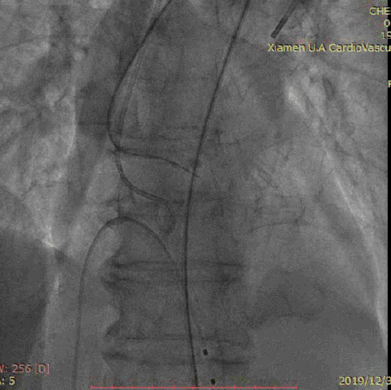

TAV8-1722球囊扩张

释放VenusA-Valve L26瓣膜

瓣膜释放后造影